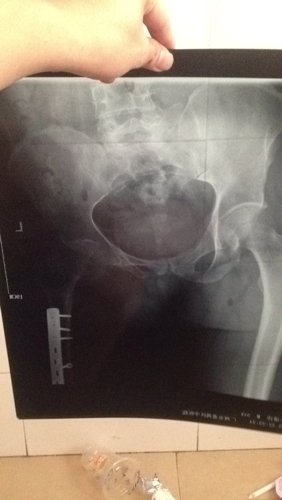

左大腿粉碎性骨折后100天内有钢板,左腿患肢有过小儿麻痹症的,今年37岁 男,前几天左大腿不小心踩了地,负了全身的重量,拍了片幸好骨折位置没有事!现在就是髋关节位置股骨交接地方 痛,很酸痛,有点硬 患腿要摆好个姿势,要不然很剧痛,已经4天了,谢谢贵人指点,谢谢